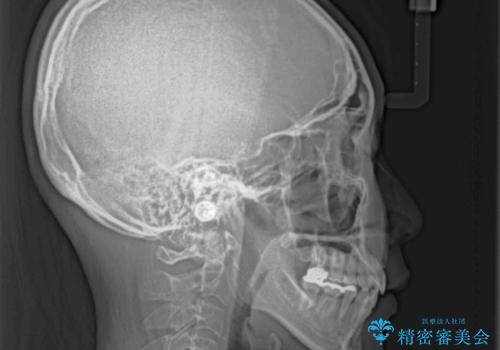

- 前歯のクロスバイトと、口元が閉じにくいとのことで来院された患者様です。

口元の突出感を改善する必要があるため、上下左右の第1小臼歯4本を抜歯し、ワイヤー装置にて矯正治療を行うこととしました。